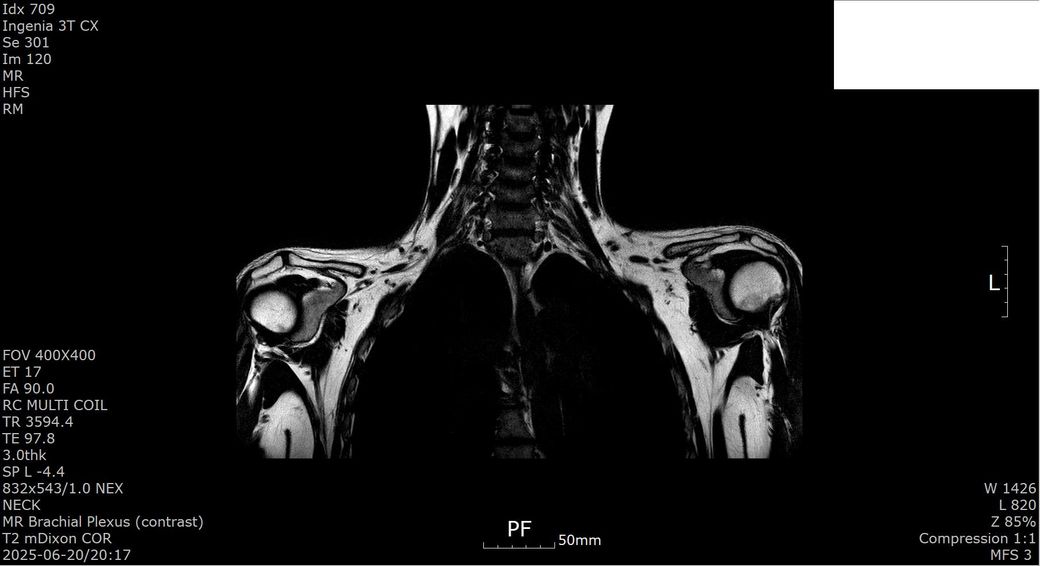

[상완신경총 brachial plexus] mri 판독 부탁드립니다

2025년 1월경 흉곽출구증후군(우측 사각근 유리술, 우측 제1늑골 제거술, 우측 상완신경총 박리술) 수술한 뒤 5개월 지난 2025년 6월경 상완신경총 mri 검사했습니다.